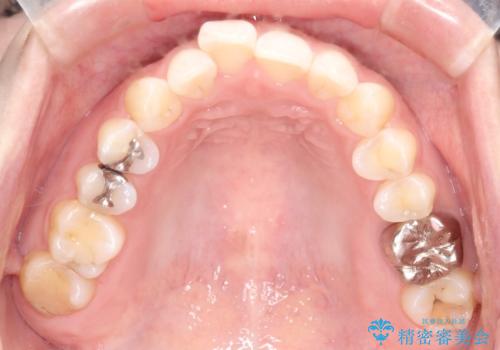

【メタルフリー】銀歯を白くしたい。オールセラミッククラウン。

- 銀歯を白くしたいと希望され来院されました。

すぐにでも白くしたいとのことで、2回目の来院で銀歯を白い仮歯に変更し喜んでいただきました。

ただ単純に白くするでけではなく拡大鏡を使用し、丁寧な処置を行なっております。